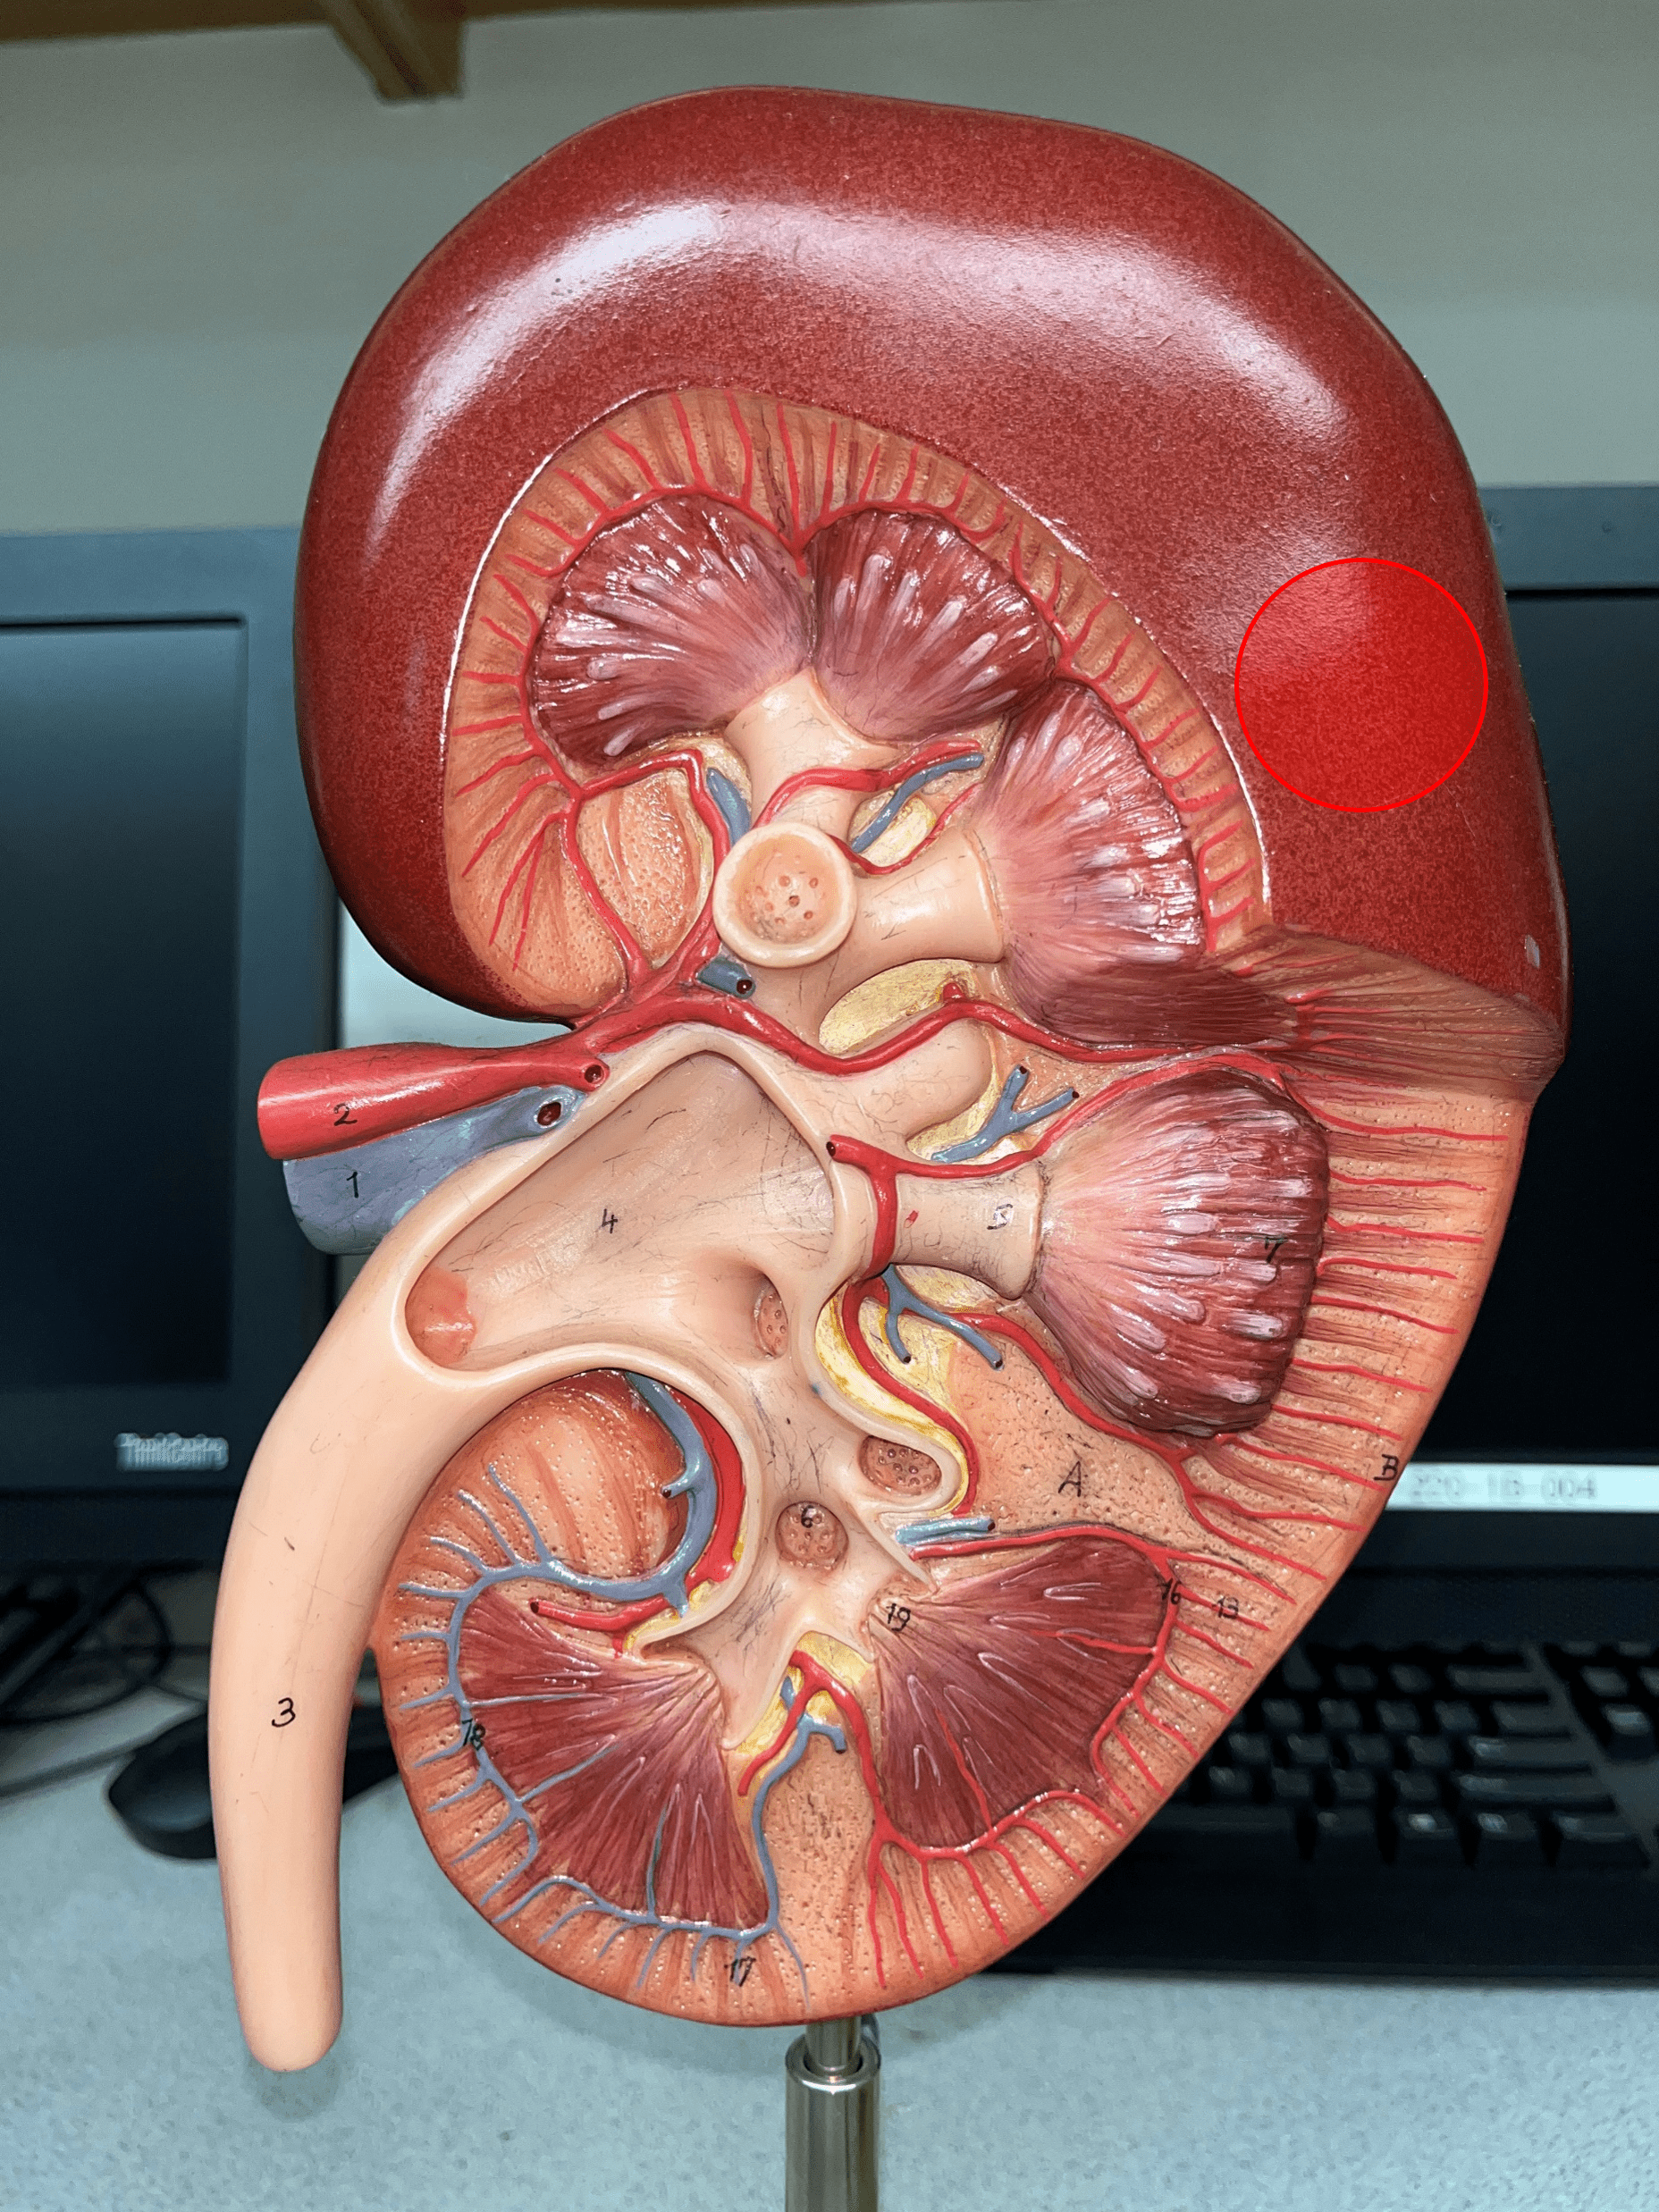

renal cortex

• The outermost region of the internal kidney.

• Superficial to the renal medulla.

• Appears slightly granular.

renal medulla

• The middlemost region of the internal kidney.

• Deep to the renal cortex and superficial to the renal pelvis.

• Contains triangular renal pyramids.

• Appears striated due to the presence of tubules and ducts.

renal pyramid

• A triangular structure found in the renal medulla.

• The base faces the renal cortex.

• The renal papilla (apex) faces the renal pelvis.